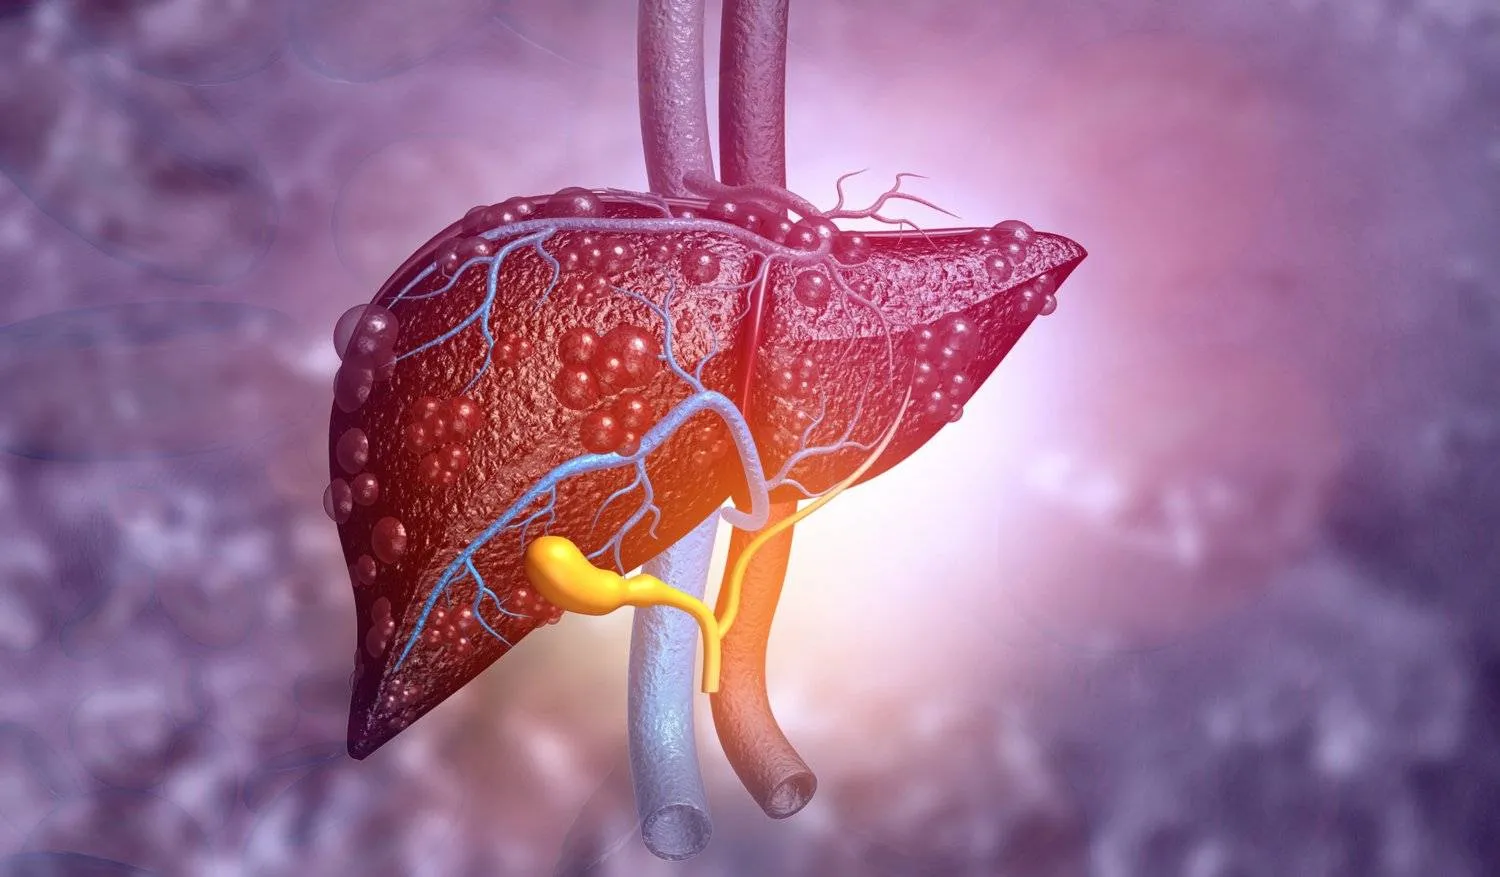

وتُعتبر أمراض الكبد من أبرز التحديات الصحية، حيث تؤثر على وظائف أساسية تشمل تنقية الدم وإنتاج البروتينات وتخزين الطاقة، بينما ترتبط بعوامل خطر شائعة مثل التدخين والكحول والسمنة والسكري والعدوى الفيروسية.

وأظهرت النتائج أن نحو 1.5 في المائة من المشاركين أصيبوا بأمراض كبدية شديدة أو احتاجوا إلى عمليات زرع كبد.